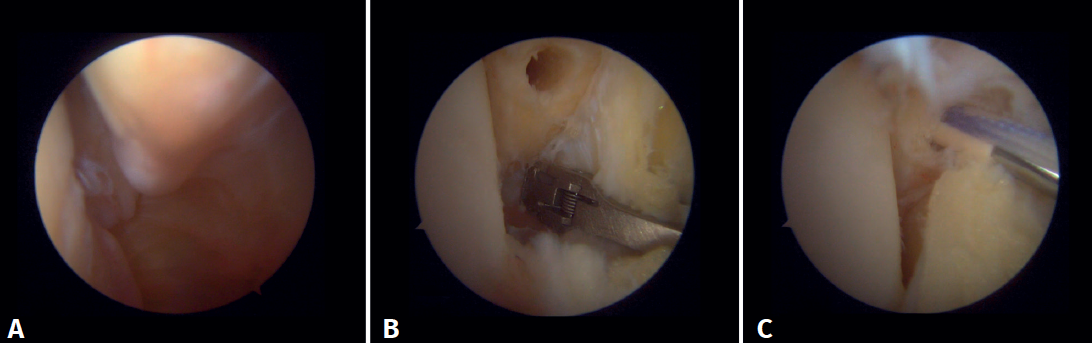

Surgical technique: arthroscopic treatment of acute medial complex injuries

In terms of surgical technique, the working portals are established in the same way as in conventional ankle arthroscopy: one anteromedial portal and one anterolateral portal. We always start with diagnostic arthroscopy to confirm the injury to the deltoid ligament. A probe can be used to verify the laxity of the fibers, and a test can be performed by inserting the probe through the medial groove: the lesion is confirmed if the instrument passes through. For repair, the viewing portal will be the anterolateral portal, thus allowing us to work more directly through the anteromedial portal. The anterior fibers of the superficial tibiotalar and intermediate fibers of the deep portion of the deltoid ligament are the ones that can be repaired with the arthroscopic technique(38). Once the ligament has been identified and dissected, a suture is passed between the fibers using a suture passer. The medial malleolus anchorage zone is prepared with a shaver or a small burr. With the ankle in neutral position, the anchor is inserted while maintaining the tension of the sutures. The intersection of the line parallel to the tibiotalar joint and a perpendicular line marked from the tip of the malleolus and along the lateral border of the malleolus can be used as an anatomical reference for placement(21). After reduction, we again test the fibers for tension and passage of the probe through the medial groove, to confirm adequate repair (Figure 8).